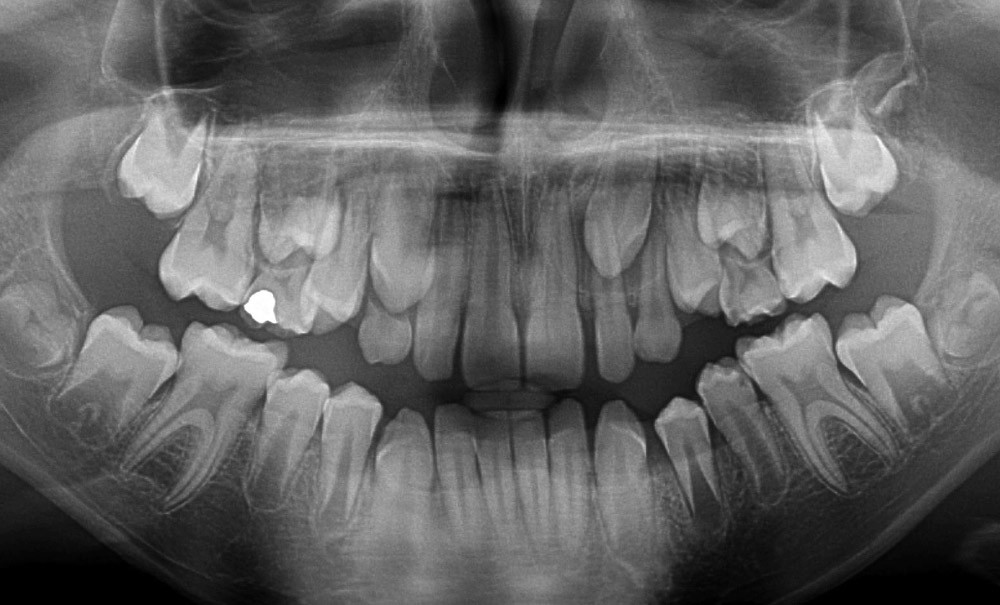

La canine maxillaire est une véritable clé de voûte de l’arcade dentaire du fait de sa situation stratégique qui lui confère des rôles esthétique et fonctionnel majeurs [1]. Après les troisièmes molaires, les inclusions de canines maxillaires sont les plus fréquentes et représentent 18 % des inclusions, soit 2 % de la population, avec une prévalence pour le sexe féminin de deux pour un [2, 3]. Sa mise en place sur l’arcade est donc un objectif majeur pour les praticiens.

Une approche prophylactique des problèmes éruptifs doit être privilégiée en sachant reconnaître les signes cliniques précurseurs comme les voussures incompressibles et indolores du maxillaire. Les images pathologiques et les trajets ectopiques doivent être diagnostiqués précocement par le biais d’un bilan radiologique.

Une fois l’anomalie décelée précocement, une attitude thérapeutique adaptée doit être mise en place, avec par exemple…